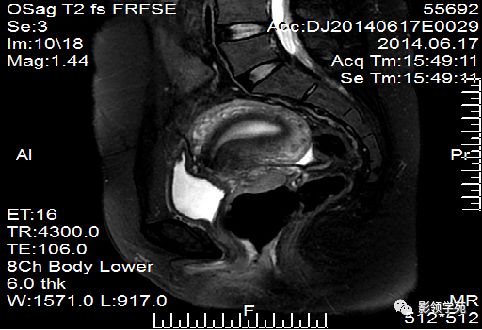

T2WI图像可显示子宫体三层

结构

- 子宫内膜-高信号

- 结合带-低信号

- 子宫肌层-中等信号

子宫体正常MRI表现

T2WI :

宫颈四层:

高信号---宫颈管黏液

稍高信号---宫颈黏膜皱襞;

低信号---宫颈纤维基质(与宫体JZ连续)

等信号---宫颈肌层